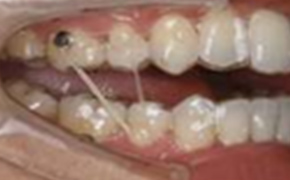

マウスピース矯正前

マウスピース矯正を行う前に準備矯正が必要な場合があります。

「第一小臼歯を抜歯後、犬歯(糸切り歯)だけを引いておく」など、ワイヤーの力を使い、動きにくい歯を動きやすい位置まで、あらかじめ移動させておく矯正です。

マウスピース矯正中

マウスピース矯正中に、マウスピースだけでは動きにくい場合は、ゴムの力を借りて歯を動かす場合があります。

また、部分的にワイヤーを使用する場合があります。